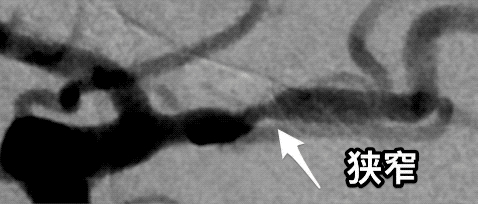

超长段椎动脉狭窄